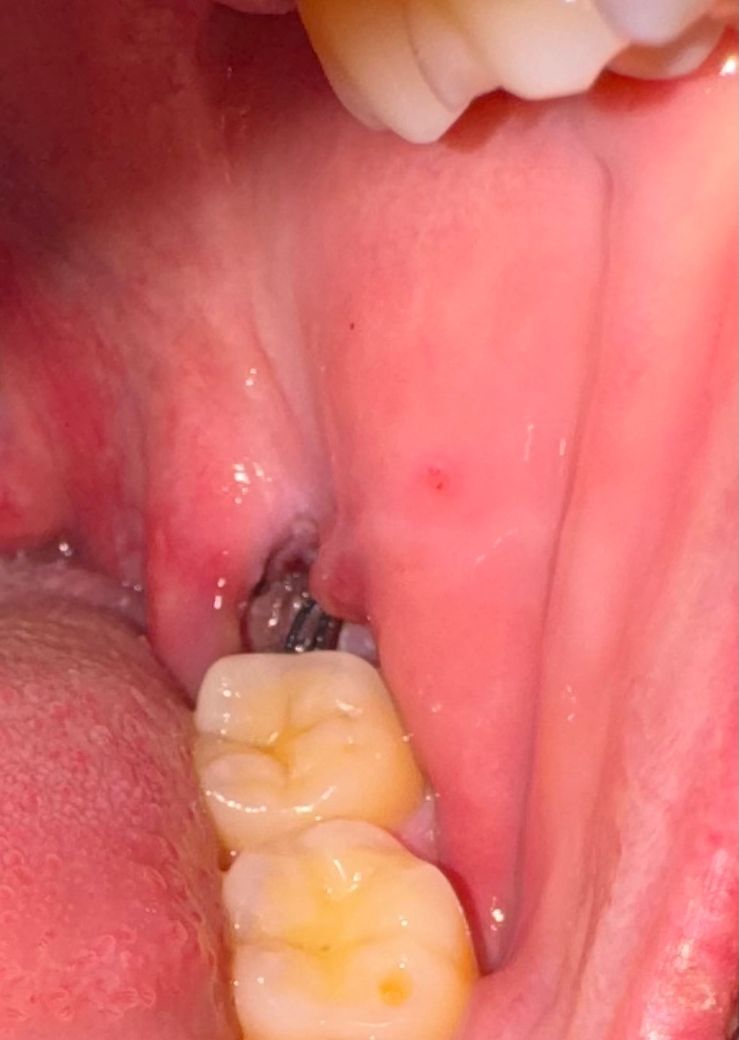

사랑니 뽑았는데 혹시 이거 혈병 탈락인가요?

음식을 먹다가 확인해보니 아침까지는 빨간색으로 딱지 비슷한 것이 있었던 것 같은데 지금은 없네요.. 혹시 이게 혈병 탈락이란 걸까요? 너무 무서워서 질문드려봅니다 ㅠㅠㅠ

사진으로 봤을 경우에는 발치를 한 후에 생긴 혈병이 탈락된것으로 보입니다. 해당 부위를 자극하지 않는 것이 좋습니다. 해당 부위가 자극이 되어 출혈이 되면 치유가 늦어질 수 있기 때문입니다. 사진으로 봤을 경우에는 큰 문제가 없으니 너무 걱정하지 않으셔도 될 것으로 생각됩니다.